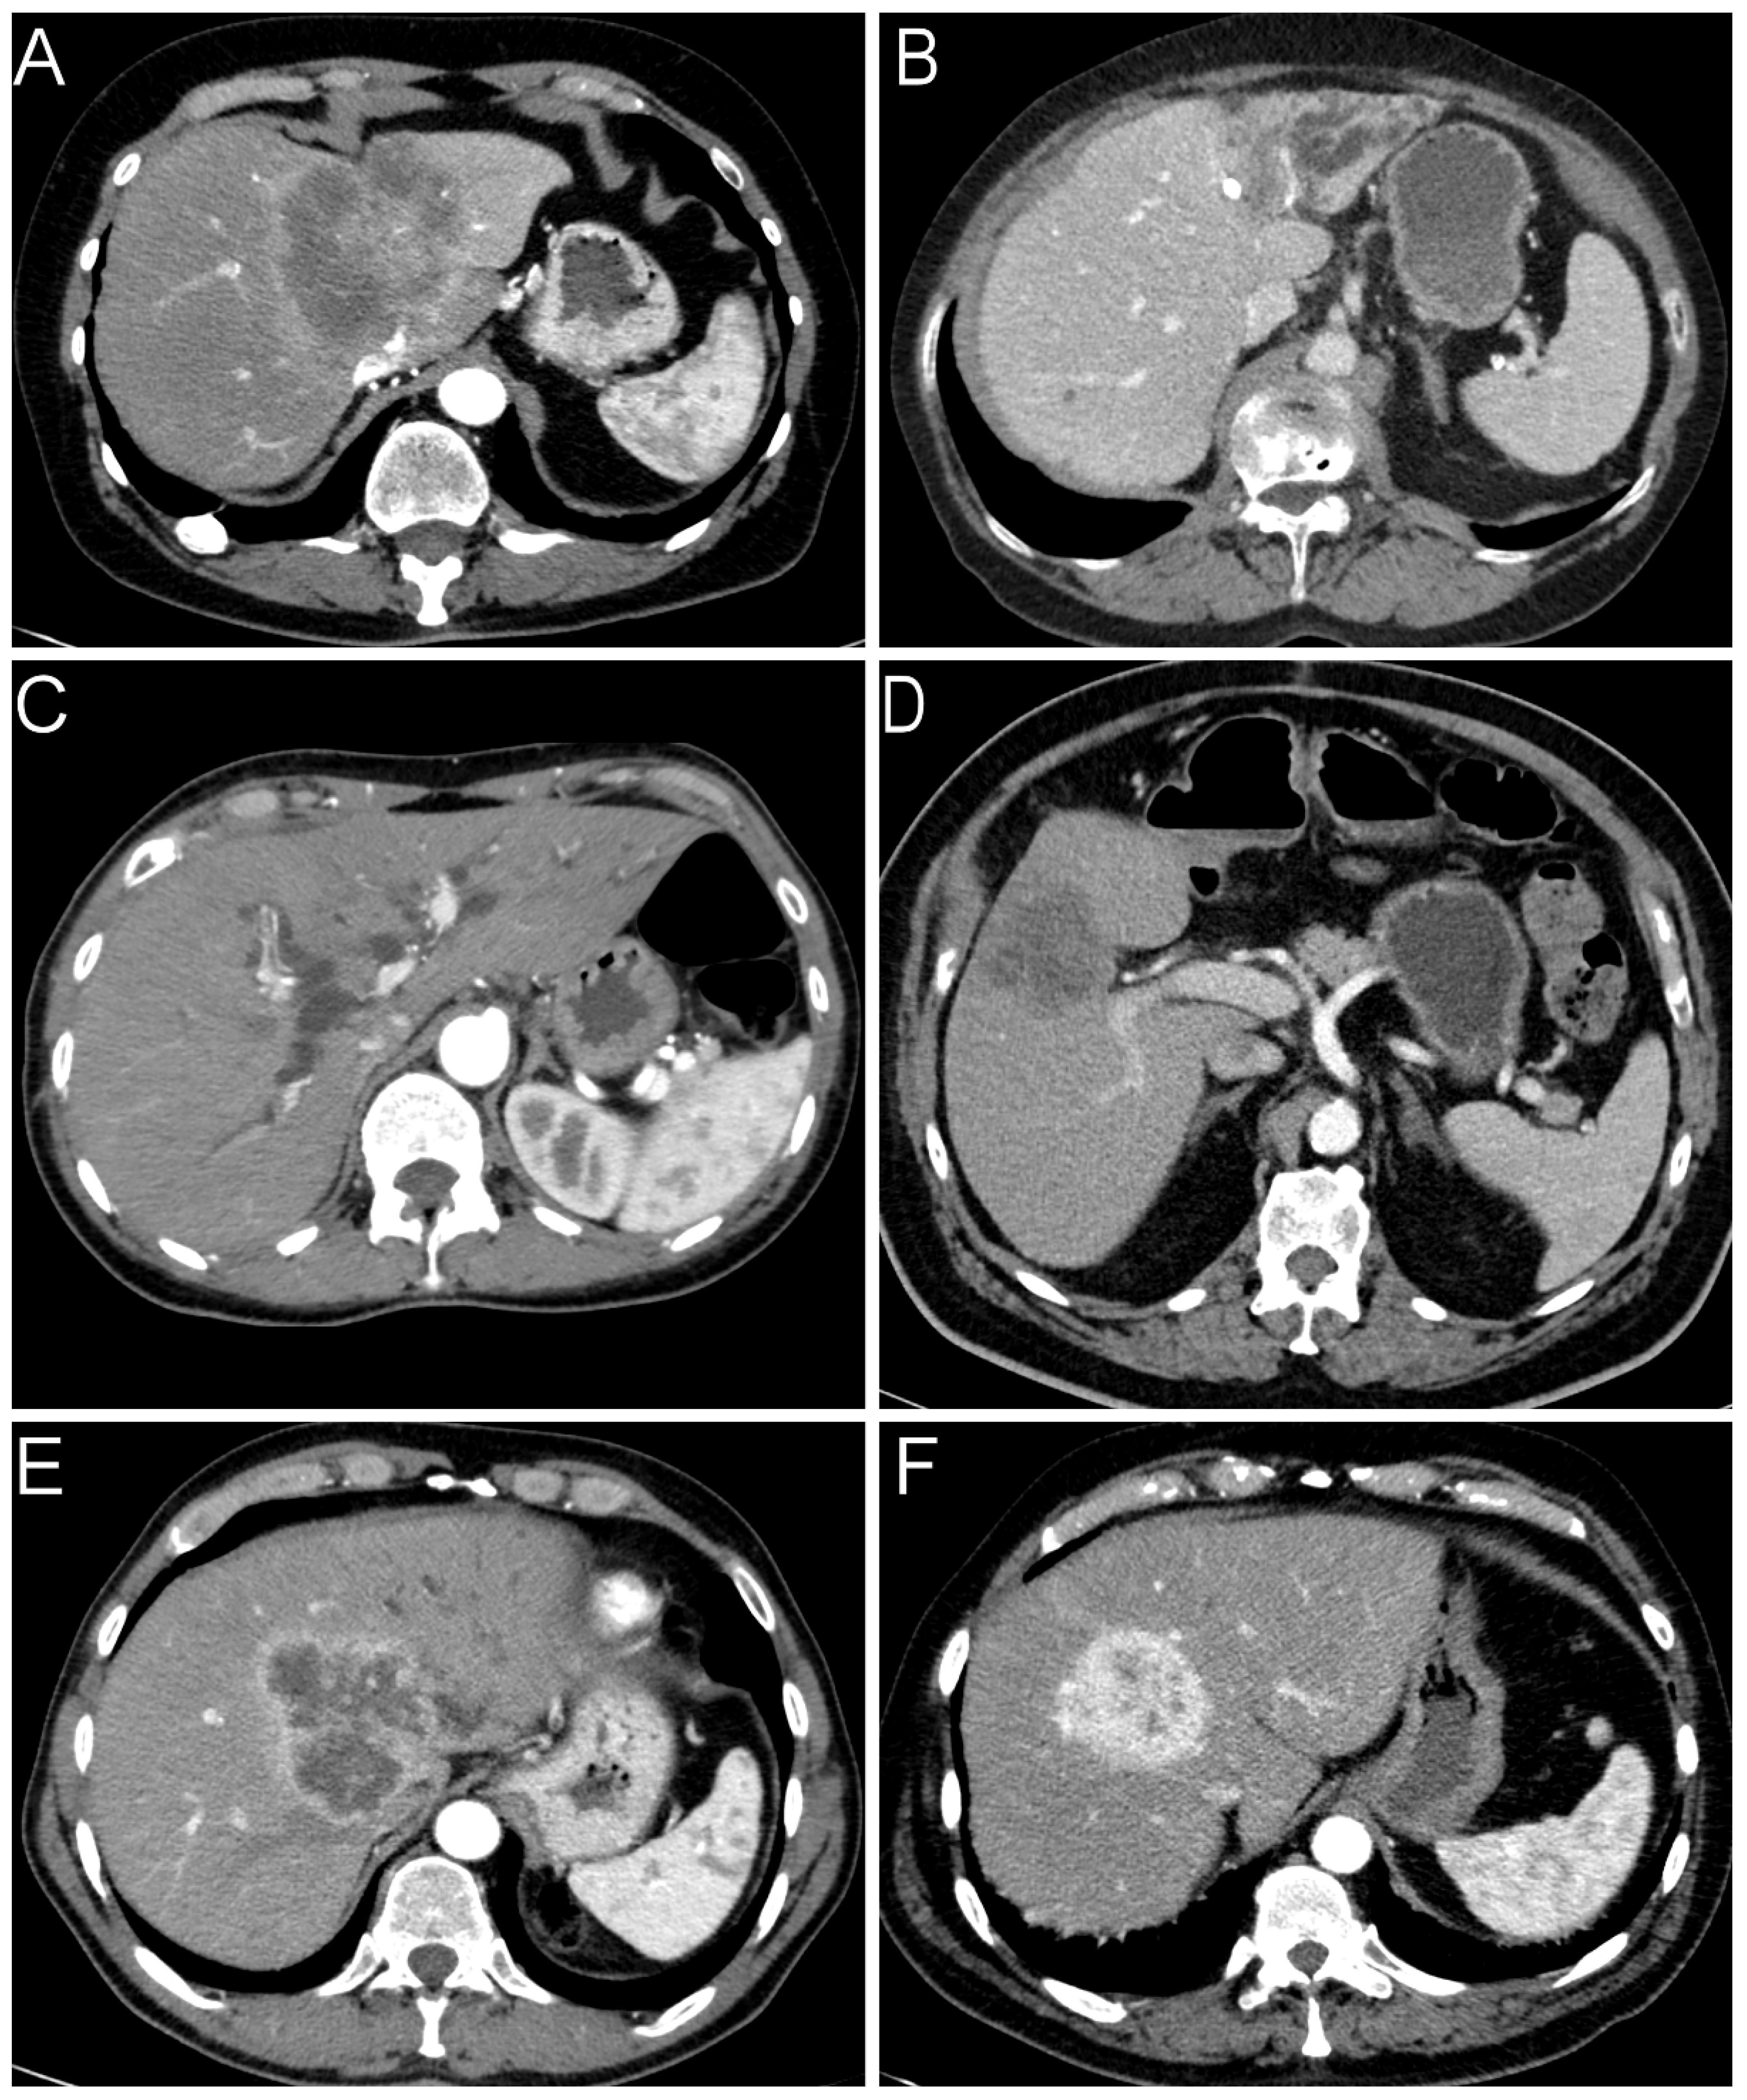

Concerning radiology, cross-sectional imaging procedures from 191 of the 232 patients were available in sufficient quality, including 146 computed tomography (CT) and 45 magnetic resonance imaging (MRI) scans. While small duct iCCAs were on average slightly larger and less frequently located near the portal bifurcation, the distance to the serosa did not show a significant difference in the comparative analysis (Table 2). Large duct iCCAs showed a duct-accentuated growth pattern in 23 cases, whereas this occurred in only three cases of small duct iCCAs. The remaining cases were classified as mass-forming (Figure 1). This difference was significant in both univariate and multivariate analyses. Ductal growth pattern correlated significantly with biliary obstruction (rs = 0.468, p < 0.001), hypovascular (rs = 0.229, p = 0.002) and rim-enhanced (rs = 0.227, p = 0.002) arterial enhancement pattern. For this reason, we excluded the parameters bile duct obstruction and contrast agent behavior from the regression analysis to avoid misinterpretation by multicollinearity. Other observed variables could not distinguish between both iCCA subtypes (Table 2). As expected, radiologic multifocality and pT2-stage (rs = 0.319, p < 0.001), invasion of visceral peritoneum and pT3-stage (rs = 0.596, p < 0.001), as well as invasion of extrahepatic structures and pT4 stage (rs = 0.361, p < 0.001) were associated, respectively.

Figure 1.

Radiological features of iCCAs. We differentiated two types of growth patterns: (A) mass-forming and (B) ductal-growing (in this case with an inserted biliary drainage). (C) Obstruction of bile ducts. Contrast agent behavior in the late arterial phase: (D) hypodense; (E) rim-enhanced; (F) hyperdense.

Imaging techniques, especially CT and MRI, naturally play a pivotal role in the management of iCCAs. Various radiologic approaches have been proposed to distinguish iCCA subtypes. However, subtype comparisons are complicated by the fact that some even recently published studies only distinguish between mass-forming iCCAs and non-mass-forming iCCAs without considering the final histopathological subtype [14,15,16,17]. In general, large duct iCCAs more often shows a ductal accentuated growth pattern with consecutive biliary obstruction [18]. On CT and MRI, large duct iCCAs typically presents as a periductal thickening and increased enhancement. In this study, we were able to provide evidence that a periductal accentuated growth pattern and the presence of biliary obstruction are the radiologically decisive factors for iCCA subtype classification. In this regard, periductal growth has been demonstrated to be strongly associated with biliary obstruction. These findings are consistent with the literature, but the present study is, to our knowledge, the first to analyze the exact histological subtypes in a blinded fashion. Akita et al. showed that the distance of tumor to portal bifurcation was largest in small duct iCCAs when compared to large duct iCCAs or pCCA [19]. In the present study, we were able to validate this observation in a larger cohort, although this measure can only serve as an approximate indicator. The tumor growth pattern was more important. Mass-forming-type iCCAs are mostly hypovascular or rim-enhanced [20,21,22]. Fujita et al. demonstrated that, in the arterial phase, tumors that showed the characteristics of large duct iCCAs had a hypovascular enhancement pattern [23]. However, in contrast to previous studies, we were not able to demonstrate a dominating arterial enhancement pattern. Most small- and large duct iCCAs present a hypovascular enhancement. Thus, there is no sufficient selectivity to differentiate iCCA subtypes. However, we detected a correlation between the periductal growth pattern and hypovascular as well as rim-enhanced pattern. This may indicate that the arterial enhancement pattern is more dependent on the individual growth pattern than the actual histological subtype.